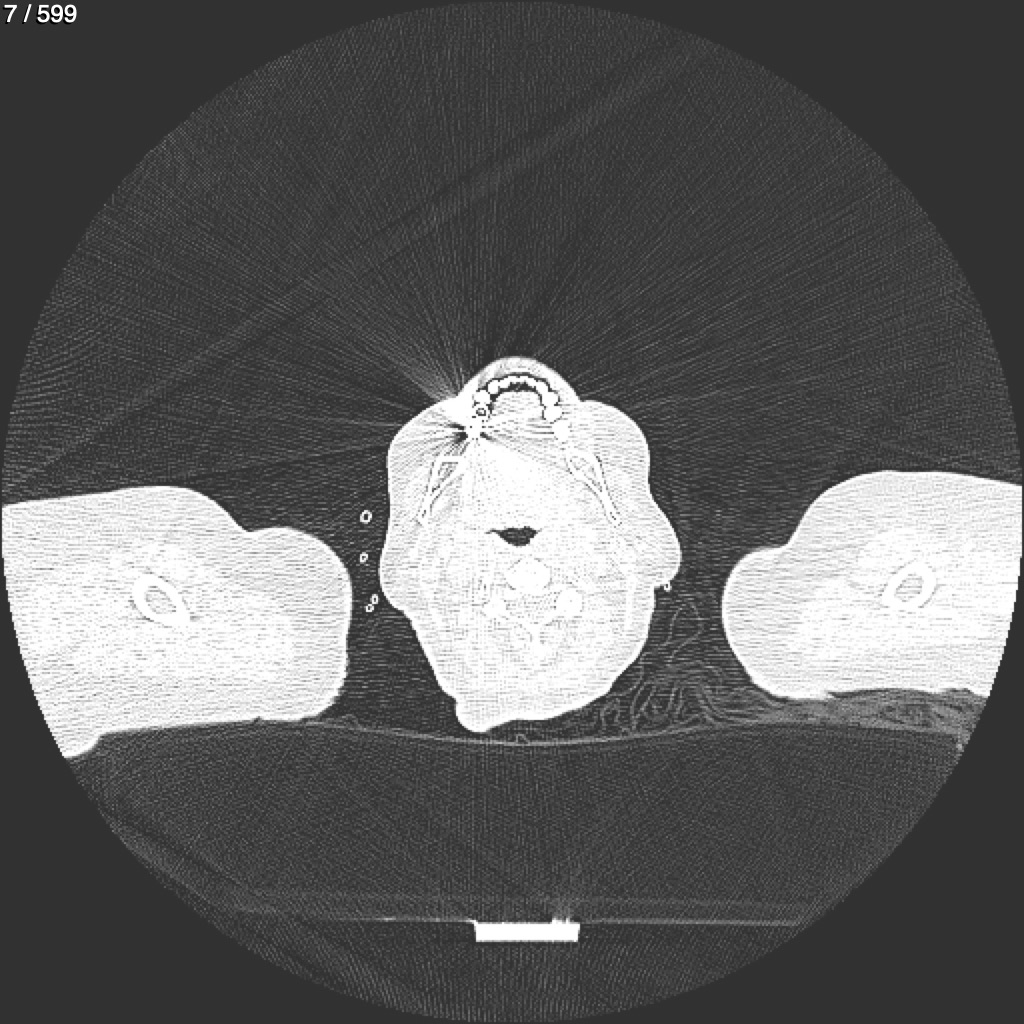

Home G​l​o​r​i​a​ ​G​l​a​d​y​s​ ​B​e​a​s​l​e​y​ ​-​ ​T​ó​r​a​x​ ​T​o​r​a​x​_​S​i​m​p​l​e​ ​(​A​d​u​l​t​o​)